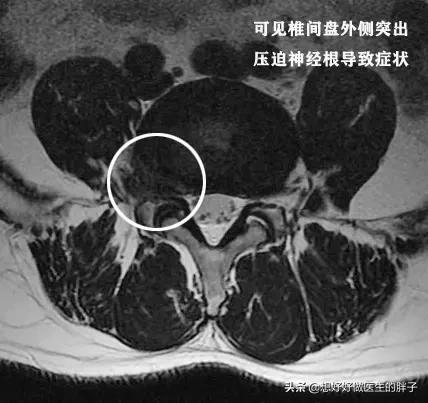

这是本人的一个患者,他本身就有腰椎间盘突出,但是不重,后来由于错误的搬动重物以后诱发剧烈的腰痛,不能正常睡觉,只能坐着才能减轻腰部以及肢体的疼痛、和麻木,后来给与其进行了椎管麻醉以后,才能平卧进行核磁,当时显示椎间盘突出属于侧方突出,压迫到了神经,单纯的看检查肯定是手术适应症。

但是给予患者进行了椎管麻醉以后,患者的疼痛明显减轻了,连续观察了5~10天,患者已经可以正常的行走了,而且一个劲的吵着要上班,后来经过劝说才复查了核磁,结果发现患者的椎间盘突出已经达到了脱出的程度,复杂的核磁上,我们看脱出的髓核已经导致了椎管出现了明显的狭窄,如此严重的情况单纯看片子是手术适应症,但是患者却没有表现出来任何需要手术的症状,所以还是保守治疗了,最近一次随访是一个月前……患者很好!